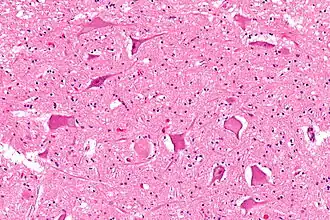

Central chromatolysis

Central chromatolysis is the most common form of chromatolysis and is characterized by the loss or dispersion of the Nissl bodies starting near the nucleus at the center of the neuron, and then extending peripherally towards the plasma membrane. Also characteristic of central chromatolysis is the displacement of the nucleus towards the periphery of the perikaryon.[3][4][5] Other cellular changes are observed during the process of the central chromatolysis. The process of Nissl dissolution is less apparent toward periphery of the cell body of the neuron, where normal-looking Nissl bodies may be present.[1] Hyperplasia of neurofilaments is frequently observed, however the extent varies. The number of autophagic vacuoles and lysosomal structures often increase during central chromatolysis. Changes can also occur in other organelles such as the Golgi apparatus and neurotubules. However, the exact significance of these changes is currently unknown. In neurons receiving axonal transection, central chromatolysis is observed in the area between the nucleus and the axon hillock following.[6]